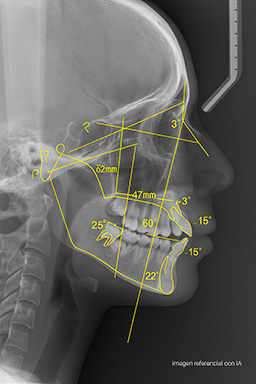

Ejemplo Estudio Cefalométrico

imagen referencial con fines didácticos

El estudio cefalométrico es un análisis radiográfico del perfil craneofacial que permite medir y evaluar las relaciones entre huesos, dientes y tejidos blandos. Es fundamental para establecer diagnósticos ortodóncicos precisos, planificar tratamientos personalizados y realizar seguimiento en cirugías ortognáticas o casos complejos de ortodoncia.